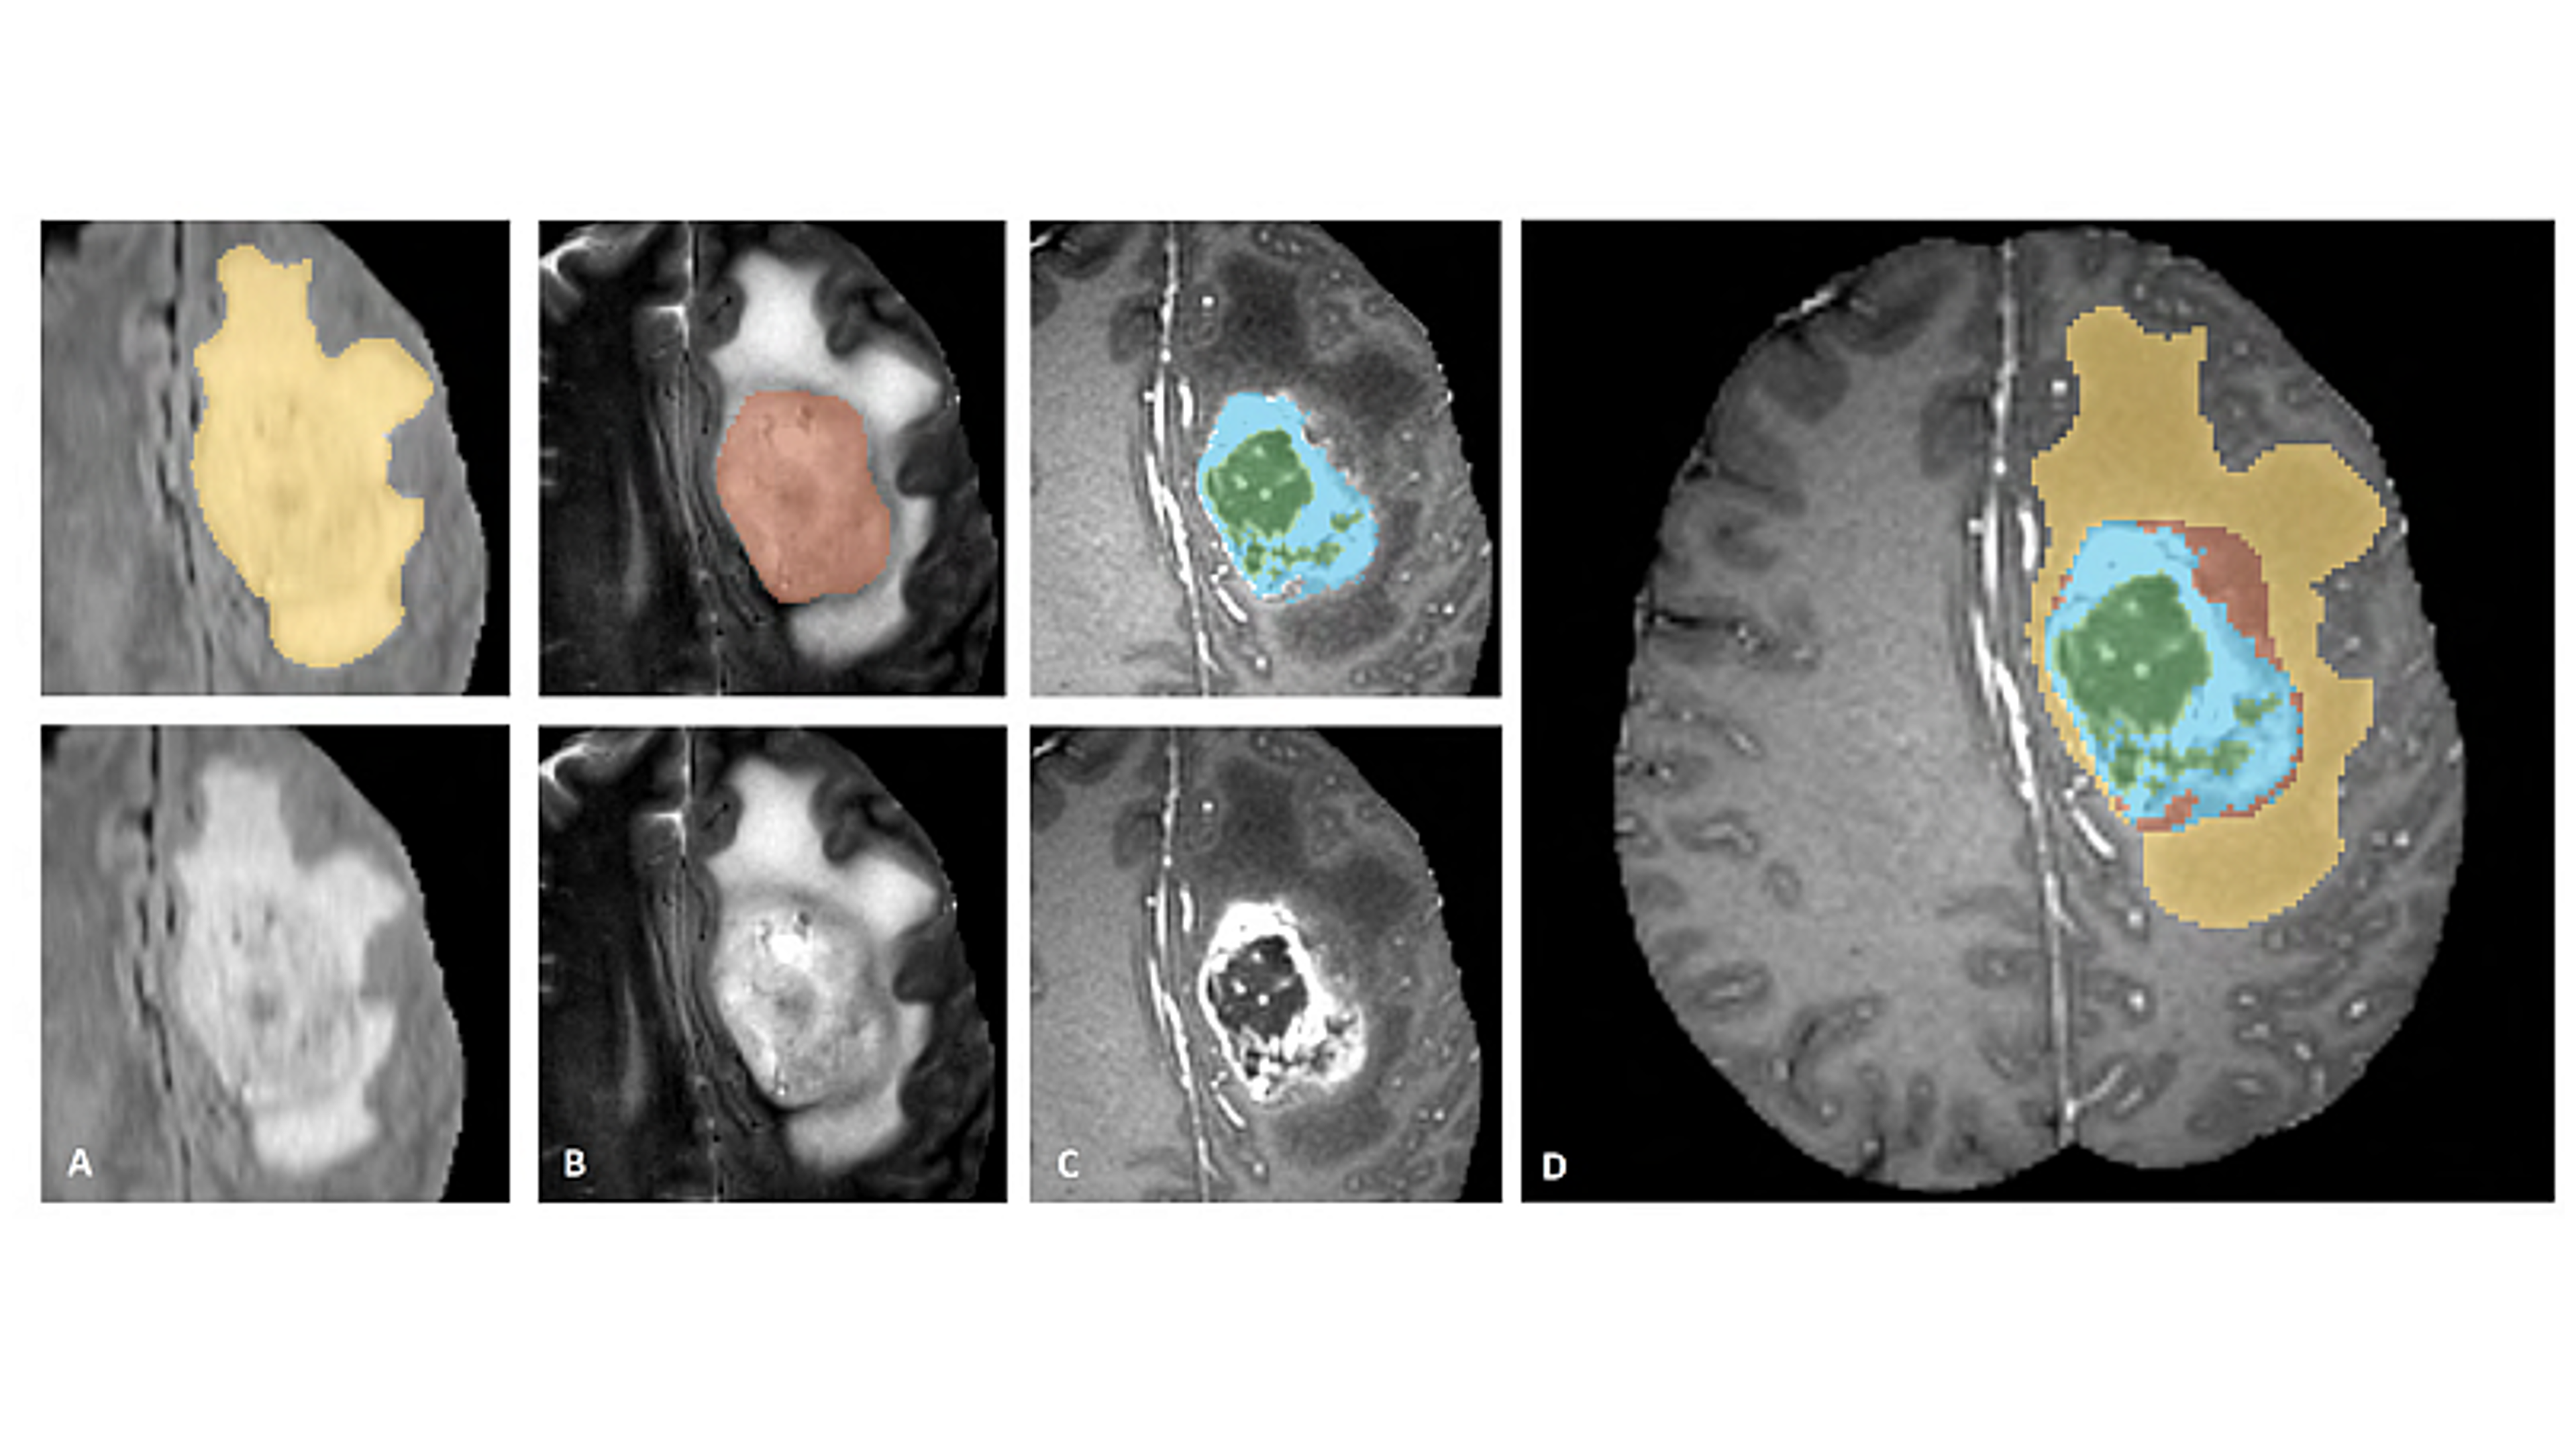

1. lin2021path.png

Lin, F. , Wu, Qiang, Liu, Ju, Wang, Dawei, and Kong, Xiangmao (2021). Path aggregation U-Net model for brain tumor segmentation. Multimedia Tools and Applications, 80(15):22951–22964.

Lin, F. , Liu, Ju, Wu, Qiang, Kong, Xiangmao, Khan, Waliullah, and 2 more authors. (2019). FMNet: feature mining networks for brain tumor segmentation. 2019 IEEE 31st International Conference on Tools with Artificial Intelligence (ICTAI):555–560.

2. shi2019brain.png